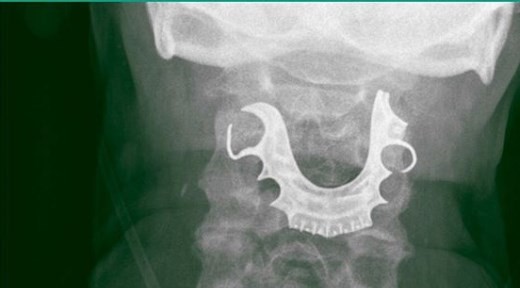

Un hombre de 72 años tuvo que ser intervenido quirúrgicamente debido a que, durante una operación, se tragó la dentadura postiza, la cual quedó atascada en la faringe.

El individuo permaneció con la placa durante ocho días en la garganta, hasta que finalmente una radiografía dio con el problema que le generaba dolor y sangrado.

El insólito caso, que fue publicado por la revista BMJ Case Reports se produjo porque el adulto mayor, durante una operación para extraer un bulto en su estómago, fue anestesiado y al despertar, se dio cuenta que su dentadura postiza no estaba.

Tras ser dado de alta, a los seis días regresó al médico debido a las constantes molestias, como dolor en el cuello, sangrado y dificultad para tragar. Sin embargo, los especialistas señalaron que se trataba de una infección respiratoria, por lo cual le diagnosticaron antibióticos.